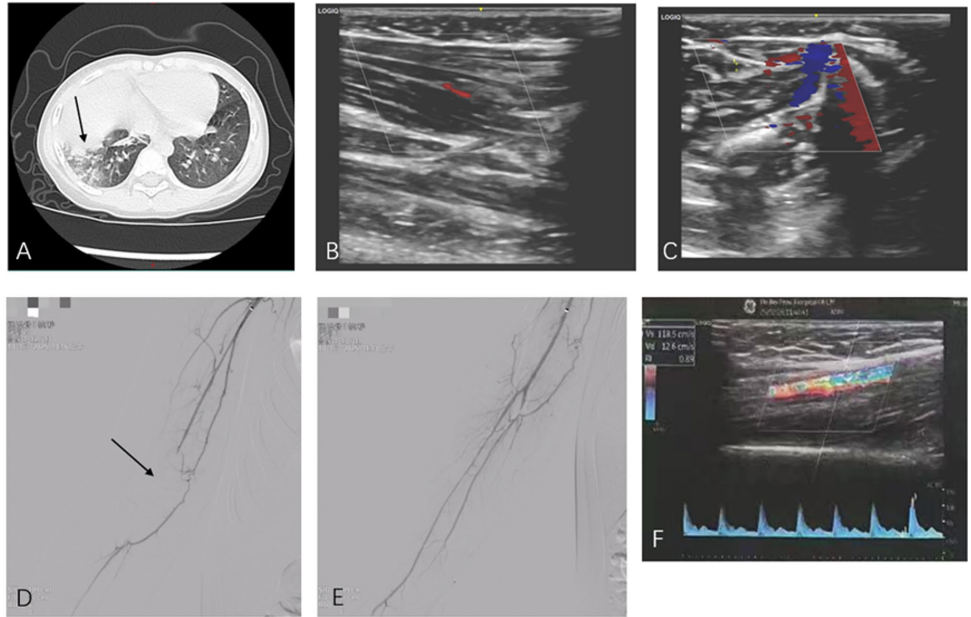

患儿因发热咳嗽5天入院,胸部CT显示右肺中下叶实变影,支气管肺泡灌洗液测序确认MP感染。治疗期间突发右上肢苍白冰冷,超声发现肱动脉远端及桡/尺动脉近端低回声血栓。

术中造影显示肱动脉、桡/尺动脉血流中断(